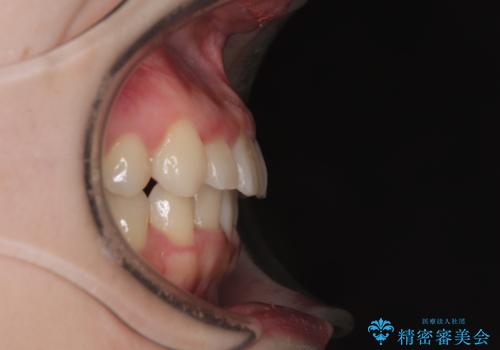

マウスピースでもワイヤー装置でも対応可能でしたが、右側の咬み合わせが上顎がやや前方に位置していることから、補助装置を使用することが推奨されました。

右上と左下の第一大臼歯2本が周辺の歯と比べて位置がずれていたため、ゴムかけやワイヤーに曲げを入れることで移動を試みましたが、どうよら癒着をしており、移動困難と判断されました。

見た目や咬み合わせに違和感がないとのことで、癒着歯の無理な移動は試みずに治療を終えることとしました。